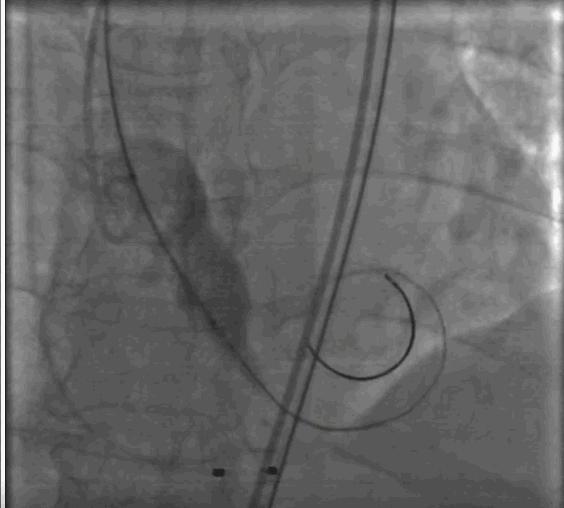

按照预先制定手术策略,首先,周玉杰教授内科团队首先进行左右冠脉保护,然后进行超硬导丝跨瓣进,23mm快速起搏预扩,左右冠脉均无显影,证实冠脉预先评估无误,选择右冠脉居中体位释放,利用瓣膜底部与无冠猪尾导管定位,快速起搏开始释放,释放至限位,由于是可回收系统进行多次反复观察评估冠脉情况,释放位置稳定较好,确认冠脉无风险完全释放瓣膜,撤出体外。

术后评估冠脉情况,瓣膜型号Downsize选择26mm恰好。无球囊后扩,主动脉瓣膜无反流,平均压差6.7mmHg。